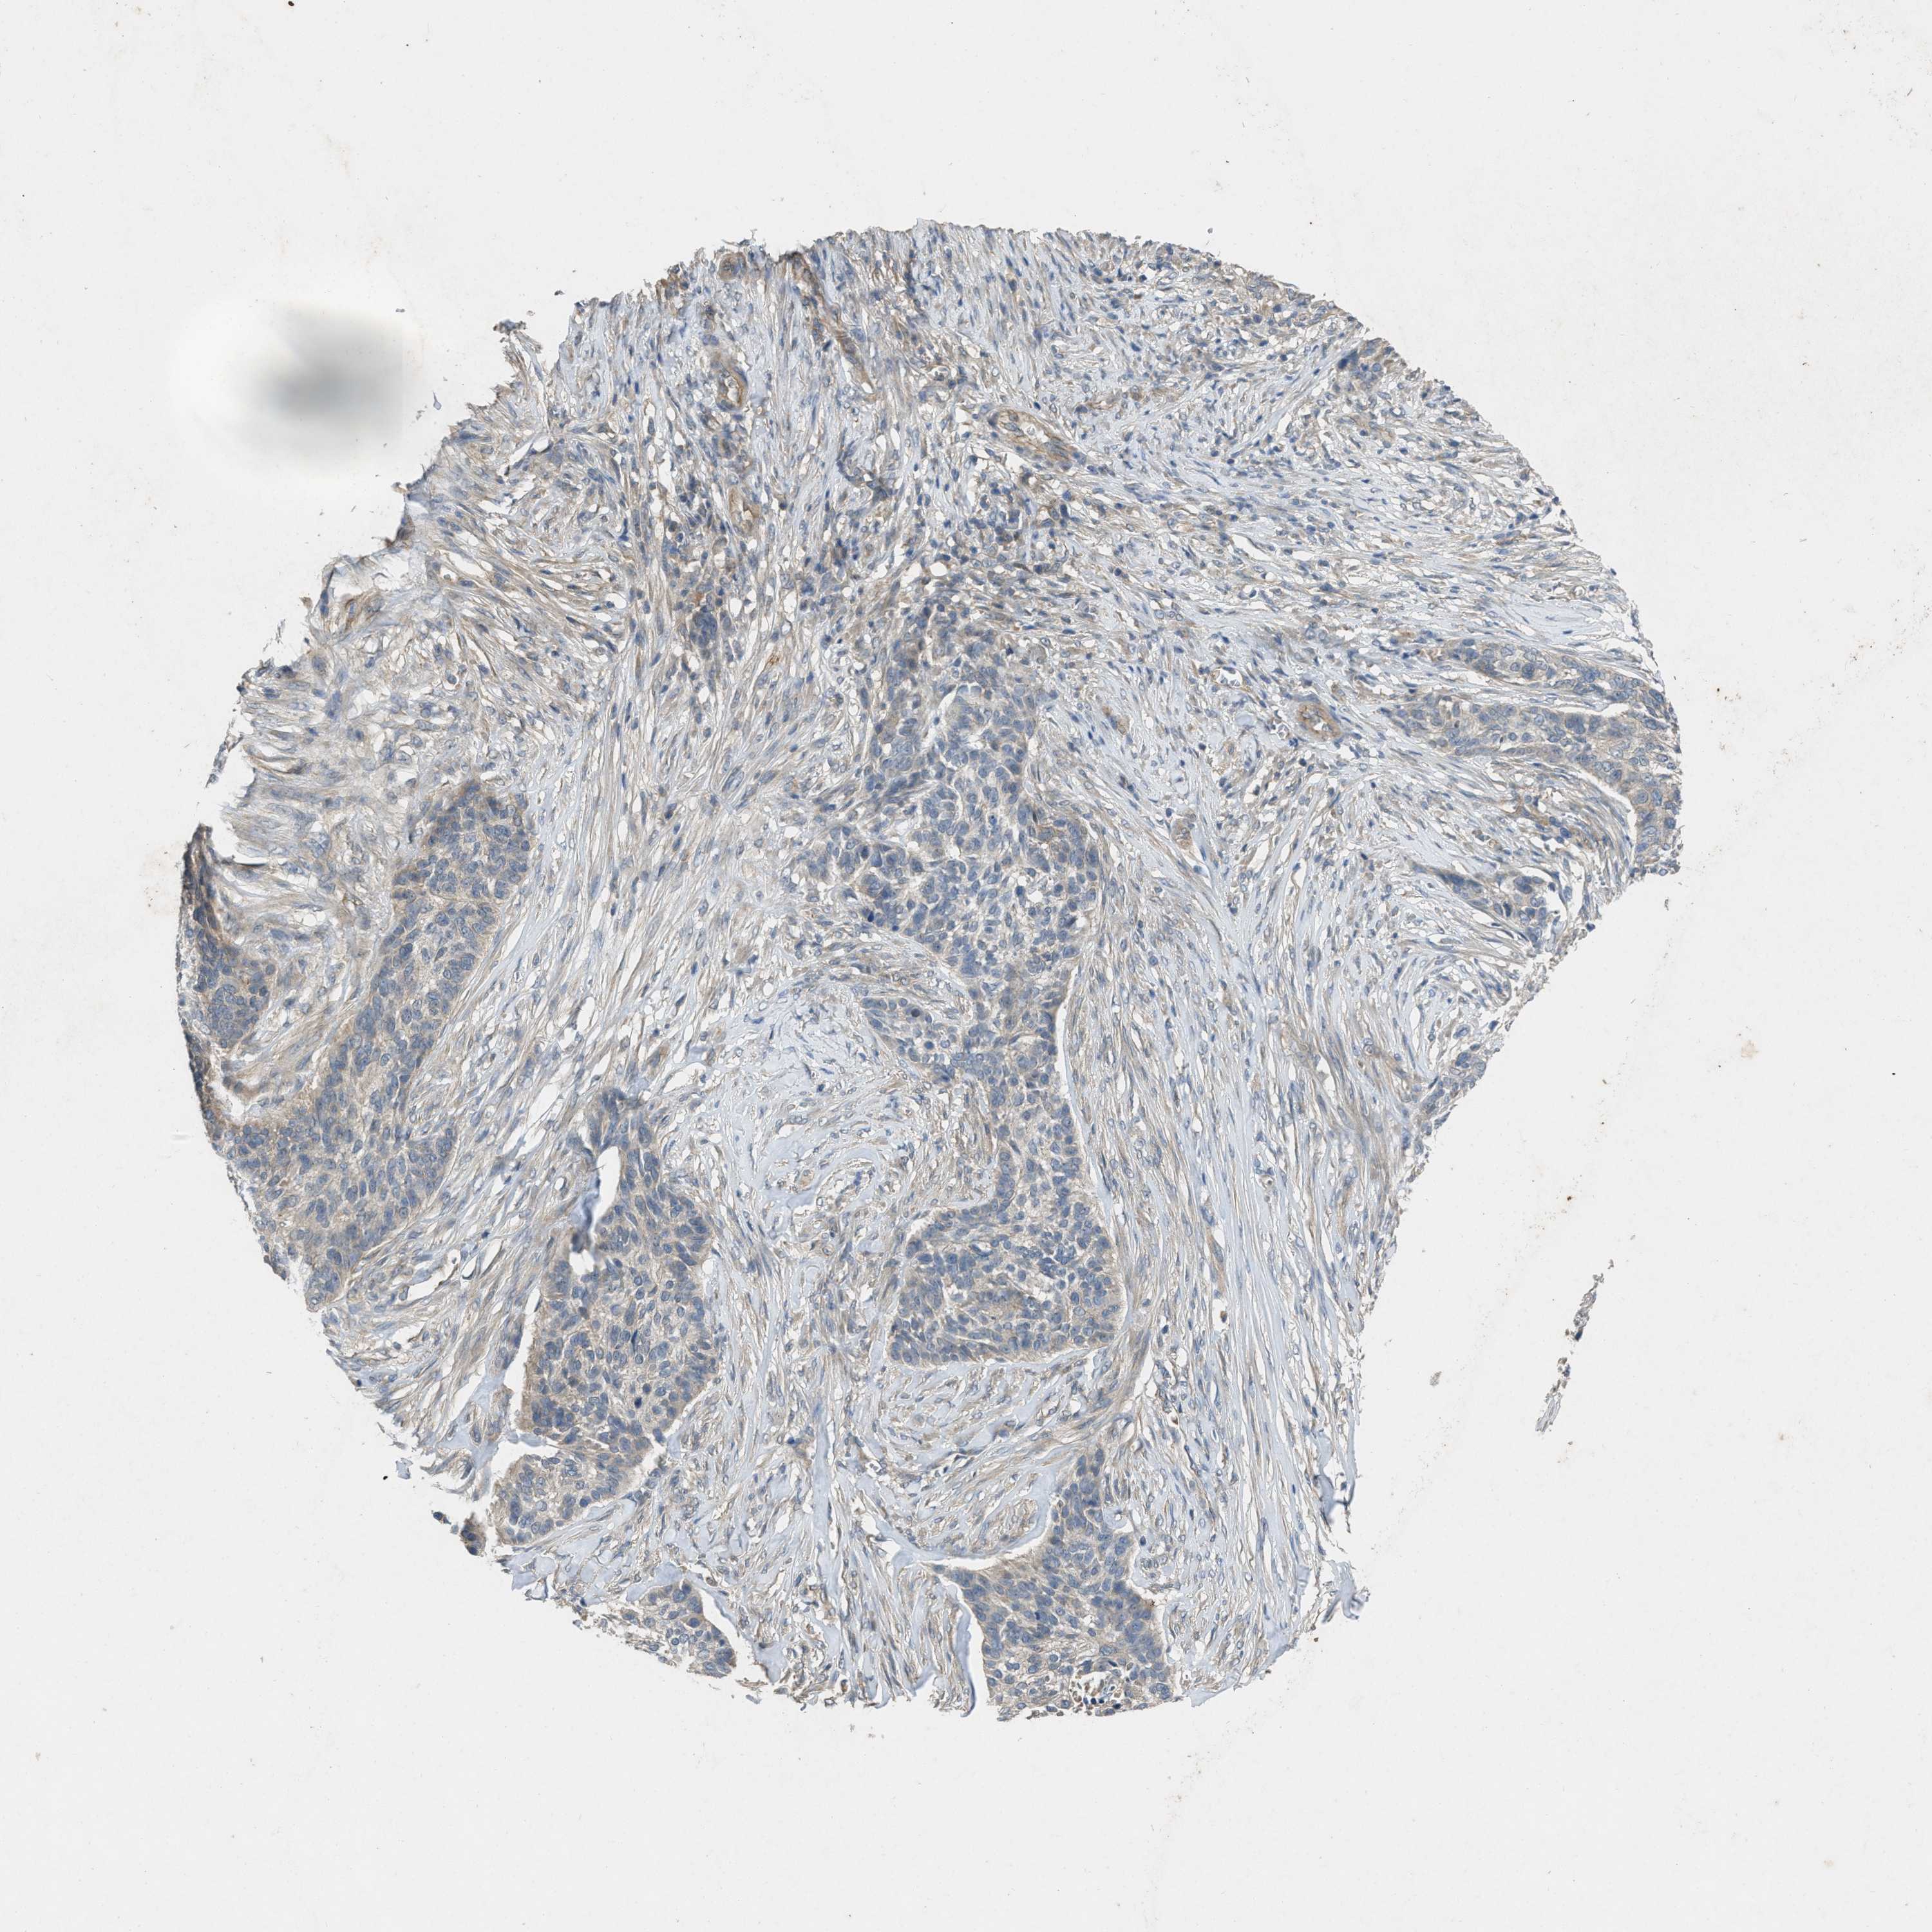

SKIN CANCER - Protein expressioni

A mouse-over function shows sample information and annotation data. Click on an image to view it in a full screen mode. Samples can be filtered based on level of antibody staining by selecting one or several of the following categories: high, medium, low and not detected. The assay and annotation is described here.

Antibody stainingi

Antibody staining in the annotated cell types in the current human tissue is reported as not detected, low, medium, or high, based on conventional immunohistochemistry profiling in selected tissues. This score is based on the combination of the staining intensity and fraction of stained cells.

Each image is clickable and will lead to virtual microscopy that enables deeper exploration of all samples and also displays staining intensity scores, fraction scores and subcellular localization as well as patient and tissue information for each sample.

Antibody HPA012778

Squamous cell carcinoma, NOS